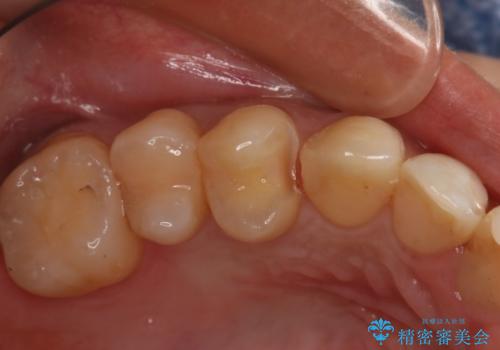

変色した詰め物の再治療 セラミックインレー

審美性と耐久性に優れたセラミックインレーで治療しました。

セラミックは素材の色調が歯に近く経年的な変色もないため、長期の審美性維持が可能となります。

セラミックインレー

歯の一部が虫歯になってしまった場合の治療法のひとつにインレーがあります。

虫歯になってしまった部分を含めて詰め物用に形を削り整え、型取りをし、出来上がってきた技工物をセメントで接着します。

自費治療では強度・色調・耐久性に優れたセラミックを使用した治療を選択する方が多いです。